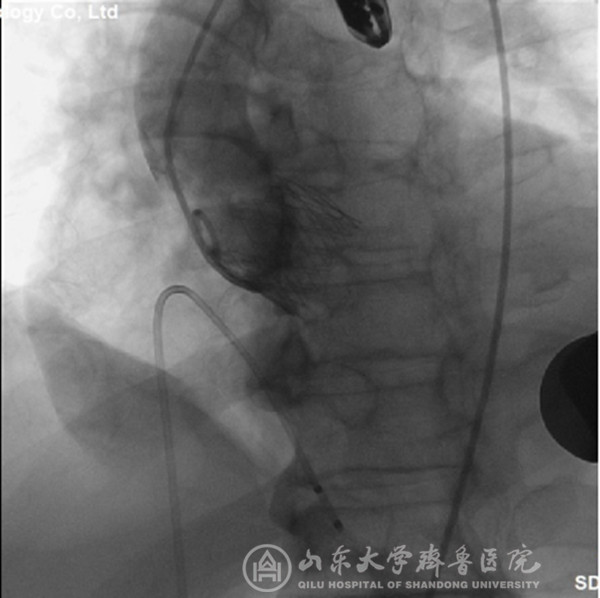

经过充分细致地准备,TAVI团队在复合手术室实施手术。根据患者的病情特点,术中做好各种应急预案,备好体外循环,维持血流动力学平稳。根据术前CT分析和术中主动脉根部造影情况(图1),选择最佳投照体位。选用29mm的介入主动脉瓣膜,经心尖途径,依次定位、顺序释放介入瓣膜(图2),造影及心脏超声检查示:人工瓣膜启闭功能正常,主动脉瓣无返流,未见明显瓣周分流(图3)。因患者心功能极差,手术操作过程中,多次出现频发及多源性室早、血压下降等情况,TAVI团队(心外科、心内科、麻醉科、手术室、心脏超声室等)医护人员齐心协力、整体配合,精心操作,积极对症处理,用时近2小时顺利完成手术。患者术后出现左心衰、血压低、尿量少等情况,给予积极处理,病情逐渐稳定。术后第2天拔气管插管,术后第5天转出监护病房。术后第7天,可下床活动,无心慌、胸闷等症状。术后第12天,病情稳定,治愈出院。术后2个月随访,患者基本日常活动不受影响,饮食正常,无心衰症状,恢复效果满意。

图3 置入介入瓣膜后,主动脉根部造影显示:主动脉瓣无返流